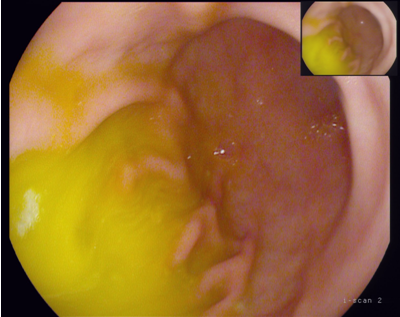

左边是看不到胆汁的胃,右边是能看到胆汁的胃,其实粘膜炎症并没有明显区别